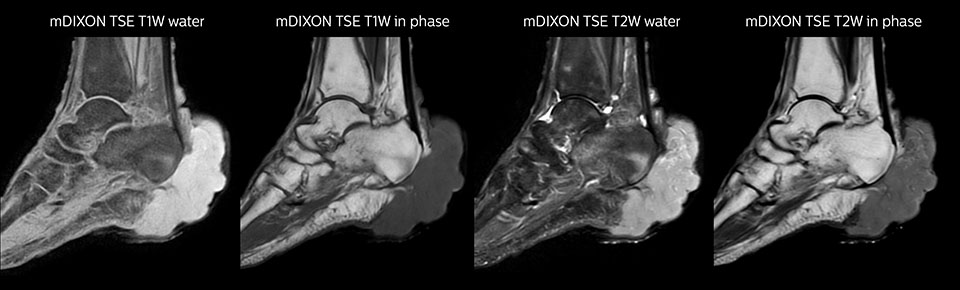

Obgleich die Region zwischen Hals und oberer Lungenspitze für ein MR-System einer der schwierigsten Bereiche ist, ergeben die mit Prodiva 1.5T erfassten Bilder bei diesem 56-jährigen Mann mit einem Pancoast-Tumor rechts eine gute Qualität. mDIXON TFE Bilder zeigen eine hervorragende Fettsuppression im Halsbereich und die diffusionsgewichtete Bildgebung enthält fast keine Verzerrungen.